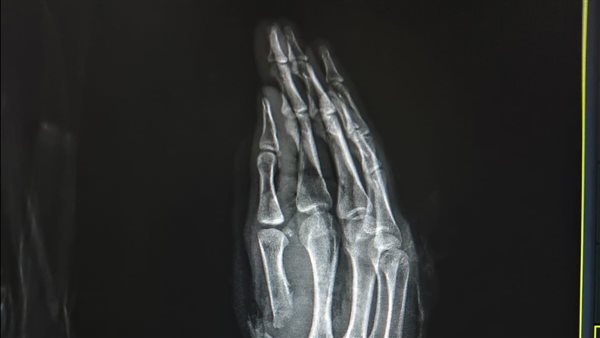

في جراحة 6 ساعات.. إنقاذ شاب تعرض لبتر كامل بإصبع الإبهام نتيجه ساطور بمستشفى سوهاج الجامعي

نجح فريق طبي بوحدة الجراحات الميكروسكوبية بمستشفى جامعة سوهاج في إنقاذ شاب يبلغ من العمر ٢٦ عامًا، مصابًا ببتر كامل في إصبع الإبهام لليد اليمنى، وقطع كامل بالشرايين والأوردة، إثر التعدي عليه بسلاح أبيض (ساطور).

ومن جانبه أوضح الدكتور مجدي القاضي عميد كلية الطب البشري جامعة سوهاج ورئيس مجلس إدارة المستشفيات الجامعية، أن الفريق الطبي نجح في إعادة زرع إصبع الإبهام باستخدام جراحة ميكروسكوبية دقيقة استغرقت نحو 6 ساعات، تم خلالها توصيل الشرايين والأوردة والأعصاب المغذية للإصبع، بالإضافة إلى تثبيت عظام الإصبع باستخدام أسلاك معدنية، مما ساهم في استعادة الدورة الدموية واستقرار الحالة.